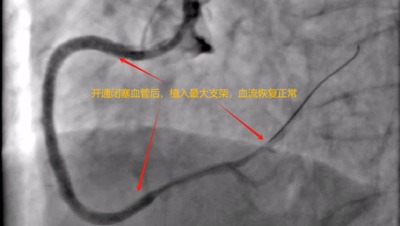

患者抵达来凤县人民医院后,取得家属同意立即被送入导管室进行手术。在心血管内科朱兴彪主任团队的协作下,凭借丰富的经验和精湛的技术,成功为患者开通闭塞血管,术后患者生命体征逐渐平稳,成功脱离生命危险。